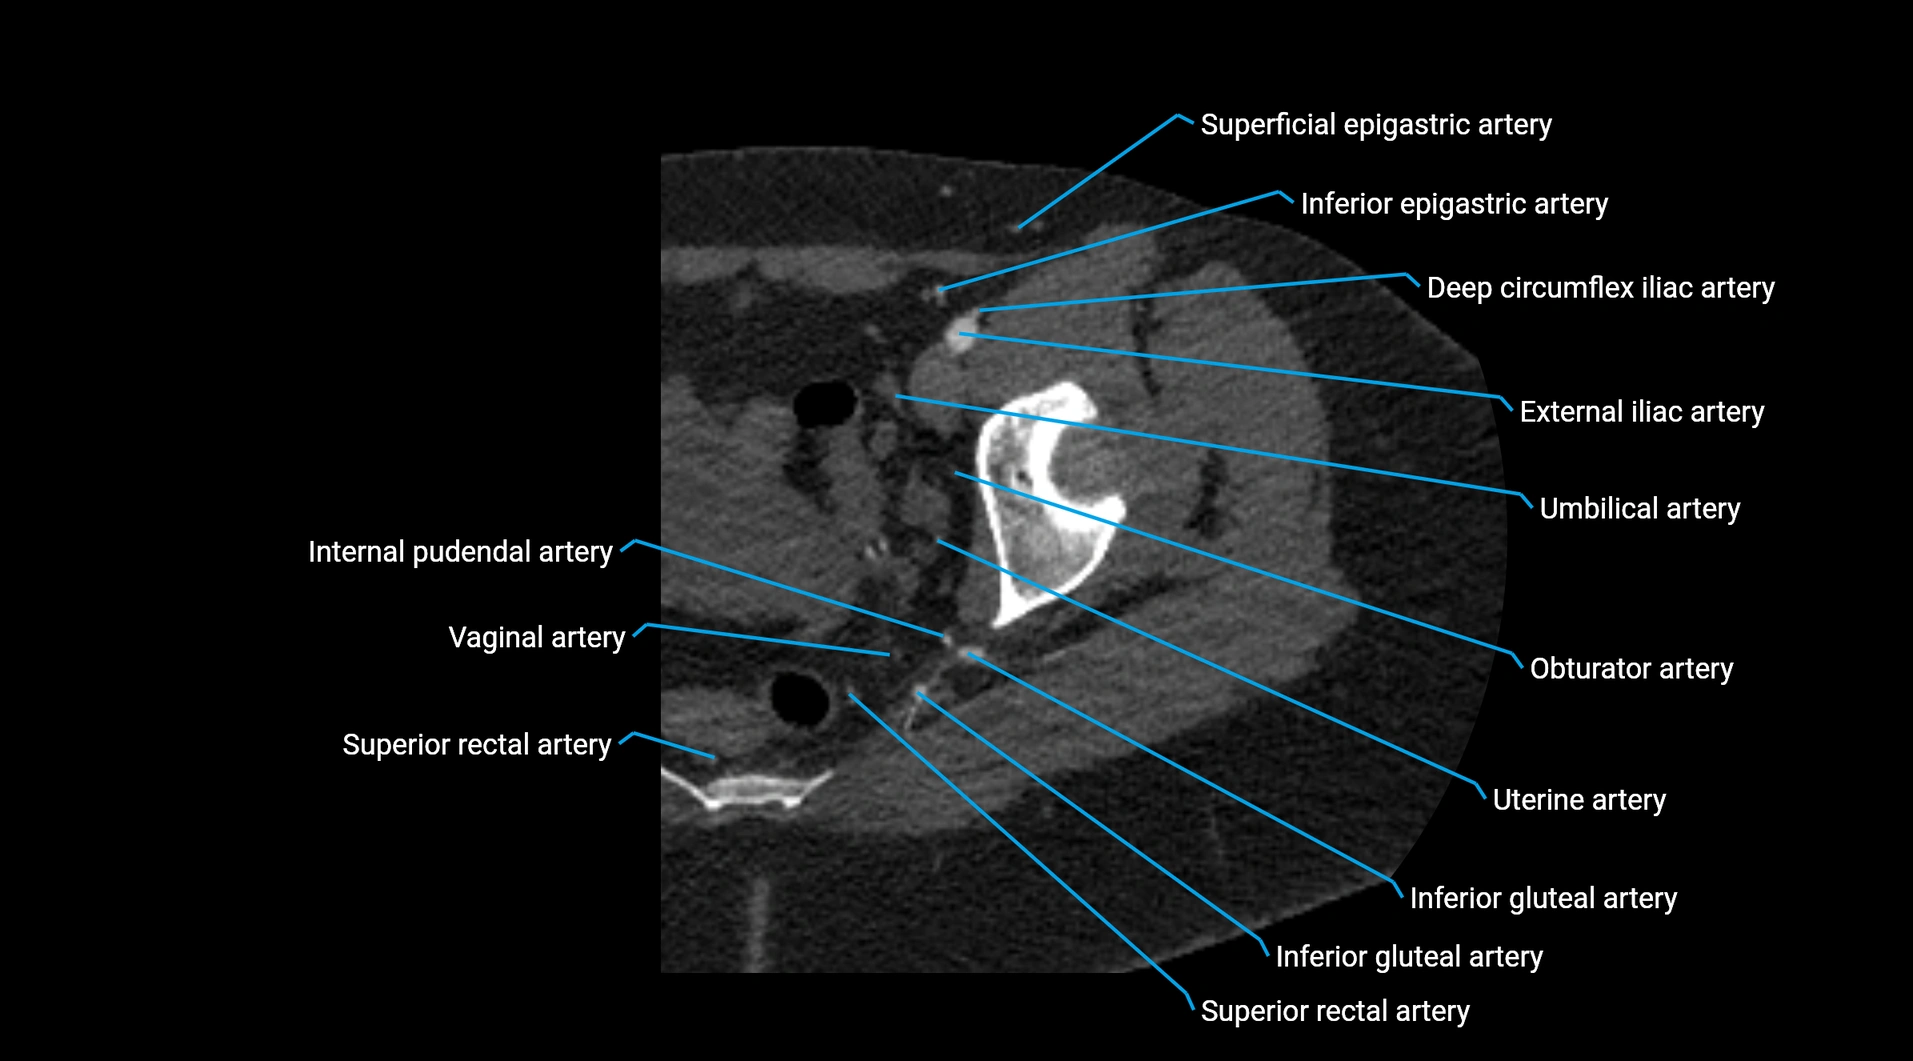

Branches

• Unpaired visceral branches: celiac trunk, superior mesenteric artery (SMA), inferior mesenteric artery (IMA)

• Paired visceral branches: middle suprarenal arteries, renal arteries, gonadal arteries (testicular or ovarian)

• Parietal branches: inferior phrenic arteries, lumbar arteries, median sacral artery

• Terminal branches: right and left common iliac arteries

Contrast-enhanced CT (CTA):

• Gold standard for abdominal aortic imaging

• Provides excellent detail of lumen, wall, aneurysm, thrombus, and branch vessels

• Multiplanar and 3D reconstructions help in aneurysm measurement, stent graft planning, and dissection evaluation

• Detects acute rupture, traumatic injury, or occlusion with high sensitivity